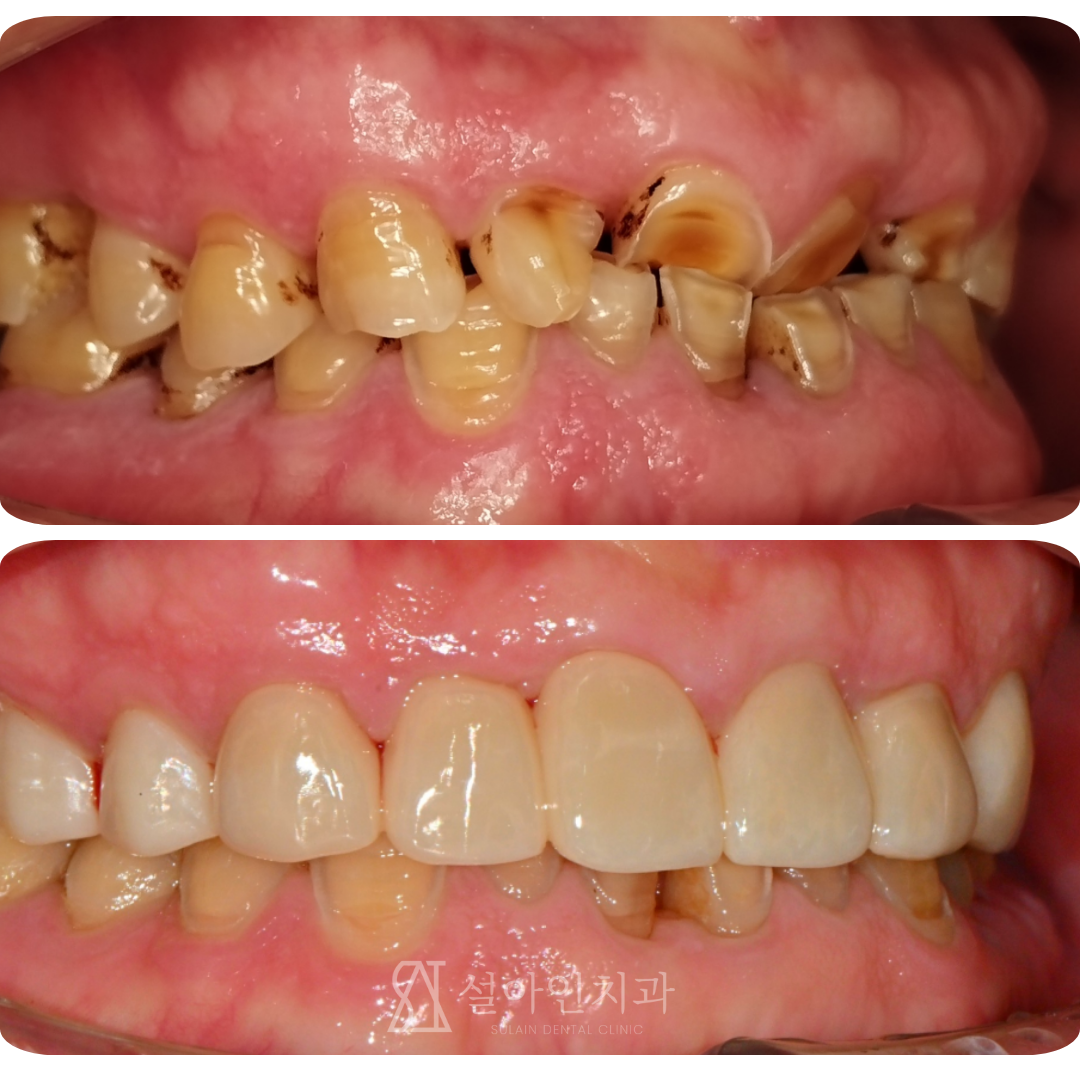

교모증으로 닳은 치아, 어떻게 회복할까?